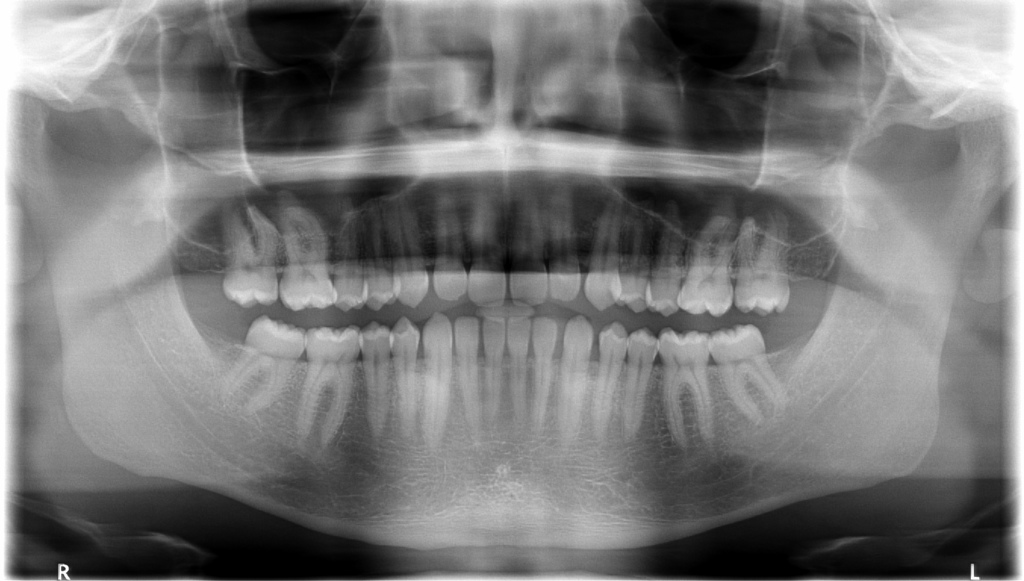

La radiologie dentaire (aussi appelée panoramique dentaire, panorex ou OTP pour orthopantomogramme) est un examen de radiologie conventionnelle qui utilise les propriétés des rayons X.

Il permet de visualiser sur un seul cliché l’ensemble des structures radio-opaques : dents, les os maxillaires supérieur et inférieur ainsi que les articulations temporo-mandibulaires.

Le matériel dentaire est également visualisé : implants, couronnes, amalgames, bridge…